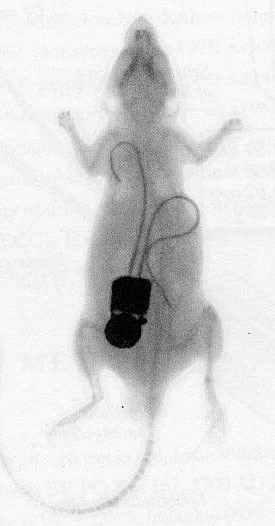

Telemetry is a way of making physiological and behavioral measures on an animal that is free to move in its cage. Telemetry involves implanting a transmitter into the abdominal cavity of the animal. This allows prolonged registration of physiological parameters such as body temperature, heart rate, and blood pressure, outside the body, without further handlingHandling Manipulating the animal, picking it up, holding it, and restraining it. of the animal. Telemetry is widely used in pharmacological research. Data gathered by means of telemetry can also be used for assessing the health status of an animal and for determining a humane endpointHumane endpoint The moment in the experiment at which pain and/or distress experienced by the investigational animal is ended or alleviated by either killing the animal humanely or by discontinuing the procedure.. Finally, it can help reduce the number of animal procedures, since an animal can be monitored over time and it can serve as its own control (see picture).

On the other hand, telemetry has drawbacks which have to be considered before one decides to set up experiments utilizing this technology. Technical possibilities combined with a desire for efficient animal use, often actually lead to an increase in the number of measurements per animal (e.g., by reusing animals), which may increase discomfortDiscomfort A state of pain and distress in laboratory animals.. The presence of the transmitter in the abdominal cavity and the (frequent) necessity of individual housing, can exert a negative influence on the animal’s welfareWelfare A complex and dynamic internal state that includes: successful biologic functioning, positive experiences, and absence of negative conditions. The animal adapts effectively to internal needs and external stimuli and maintains a good mental state. and on its behavior and physiological functions.